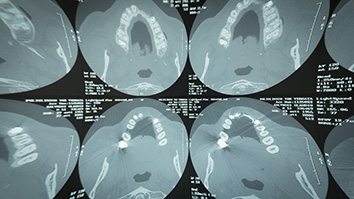

La Tac che usiamo nella nostra struttura è un apparecchio volumetrico di ultima generazione, che consente di ottenere immagini tridimensionali molto particolareggiate dei denti e delle ossa, con dosaggi molto ridotti. Infatti per “volumetrico” si intende che con un solo passaggio del tubo radiogeno si rileva il volume desiderato, che si tratti di entrambe le mascelle, oppure di uno o due denti (in questo caso con una dose di raggi x veramente minima). Le immagini ottenute sono indispensabili alla diagnosi in implantologia e parodontologia, ma si usano anche per le cure canalari difficili, quando è importante valutare la presenza di fratture o canali nascosti. Servono per programmare gli interventi di implantologia, guidata e non, e consentono valutazioni tridimensionali molto accurate delle tasche parodontali, delle cisti, dei seni paranasali e dei denti inclusi. Tutto questo con una procedura molto semplice che ci consente, in pochi minuti, di ottenere informazioni essenziali per la diagnosi ed il trattamento delle patologie dei denti e della bocca.